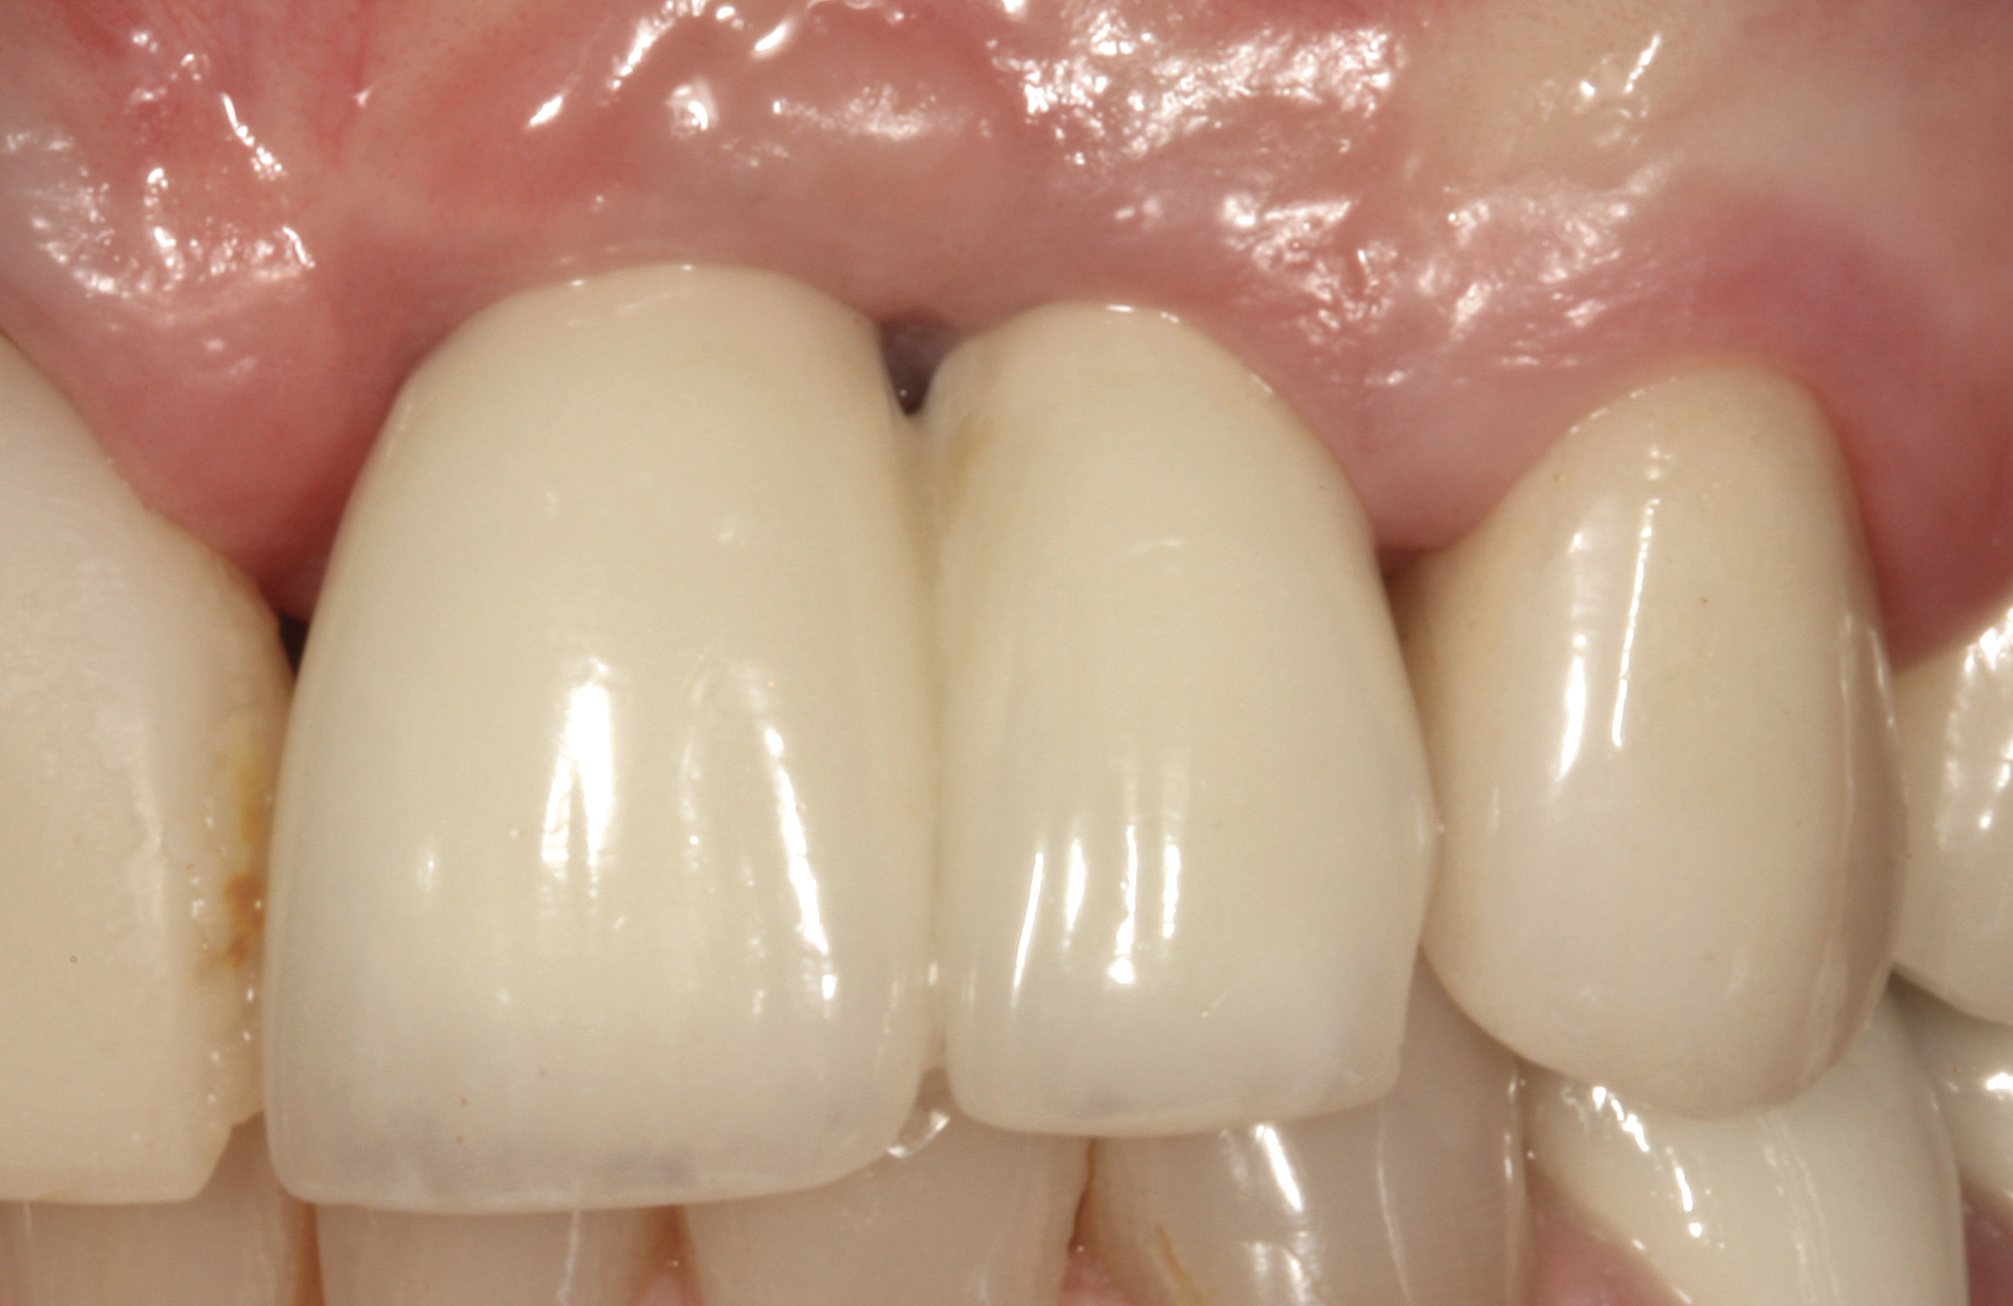

It was determined that additional augmentation was required to increase the soft-tissue volume, so a subepithelial connective tissue graft was acquired from the palate (Figure 8),23,24 placed, and allowed to mature for at least 3 months. Second-stage implant undercovering surgery with a palatal-biased incision was performed after tissue maturation to further thicken the labial soft tissues. In addition, a flat contoured healing abutment was placed to allow the soft tissues to mature without risk of recession, and the RBR replaced (Figure 9). After 4 to 6 weeks of healing, a flat contoured screw-retained provisional restoration was inserted (Figure 10) with the proper submergence profile to restoratively sculpt the soft tissues. An implant-level impression was made and the definitive cement-retained metal-ceramic restoration fabricated and inserted (Figure 11 through Figure 13). The final esthetic outcome to restore the proper length and proportion of the right lateral incisor to match that of the contralateral incisor was accomplished using the treatment steps outlined above, where the mucosal tissues were augmented after implant decoronation (Figure 14).

Fig 45. The definitive crown tooth No. 26 seated in place and provisionally cemented. The recession defect was eliminated with the removal and replacement of a new implant in the proper position.

Figure 45